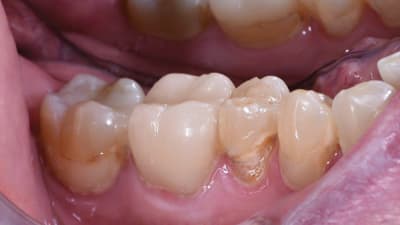

Products in Practice Restorative Digital Workflow Across Multiple Practices Achieves Efficient and Esthetic Results By Laura Justice, DMD June 01, 2020 13 min read